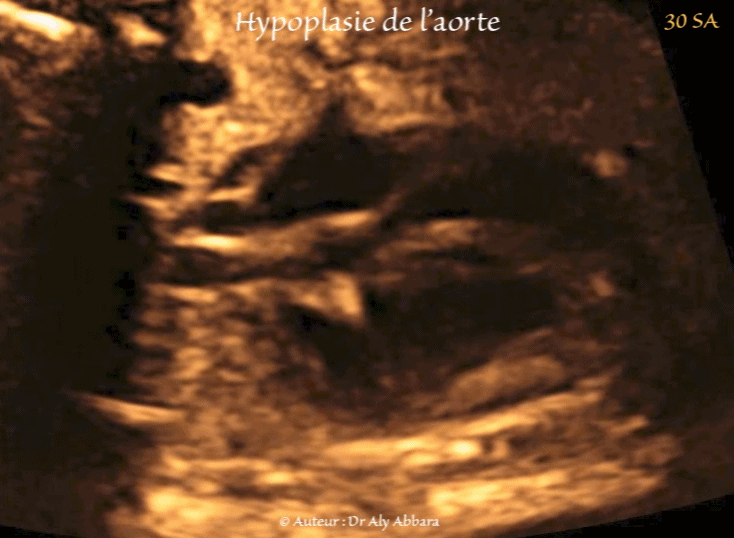

• Images échographiques montrant des multiples signes échographiques liés à la présence d'une hypoplasie de l'aorte dans sa portion ascendante et horizontale.

• Hypoplasie de l'aorte ascendante et de crosse de l'aorte : elle est visible sur la coupe des trois vaisseaux et de la trachée :

• le diamètre de l'aorte ascendant = 3,4 mm ;

• le diamètre de l'aorte horizontale = 2,5 mm ;

• à titre de comparaison, le diamètre du tronc pulmonaire = 8,5 mm.